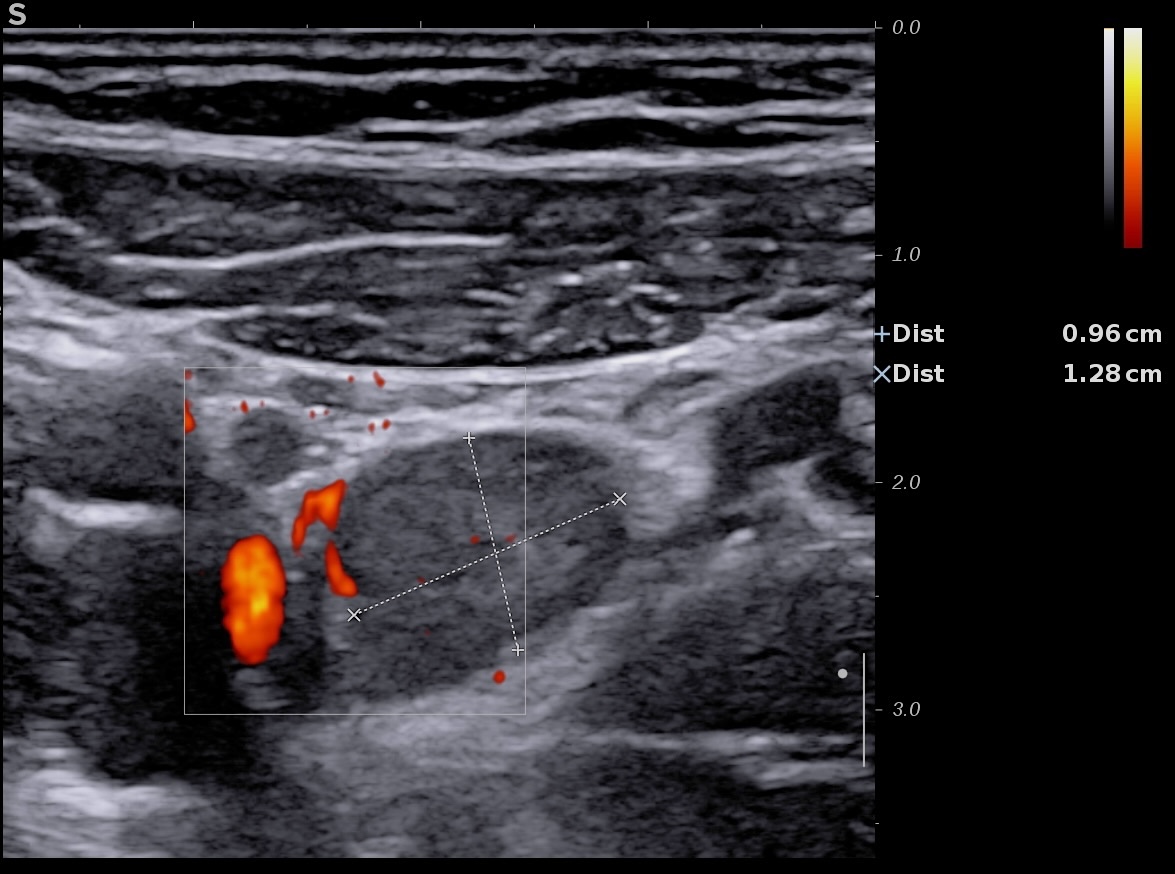

Ci-dessous volumineux ganglion (9,6 mm) inflammatoire